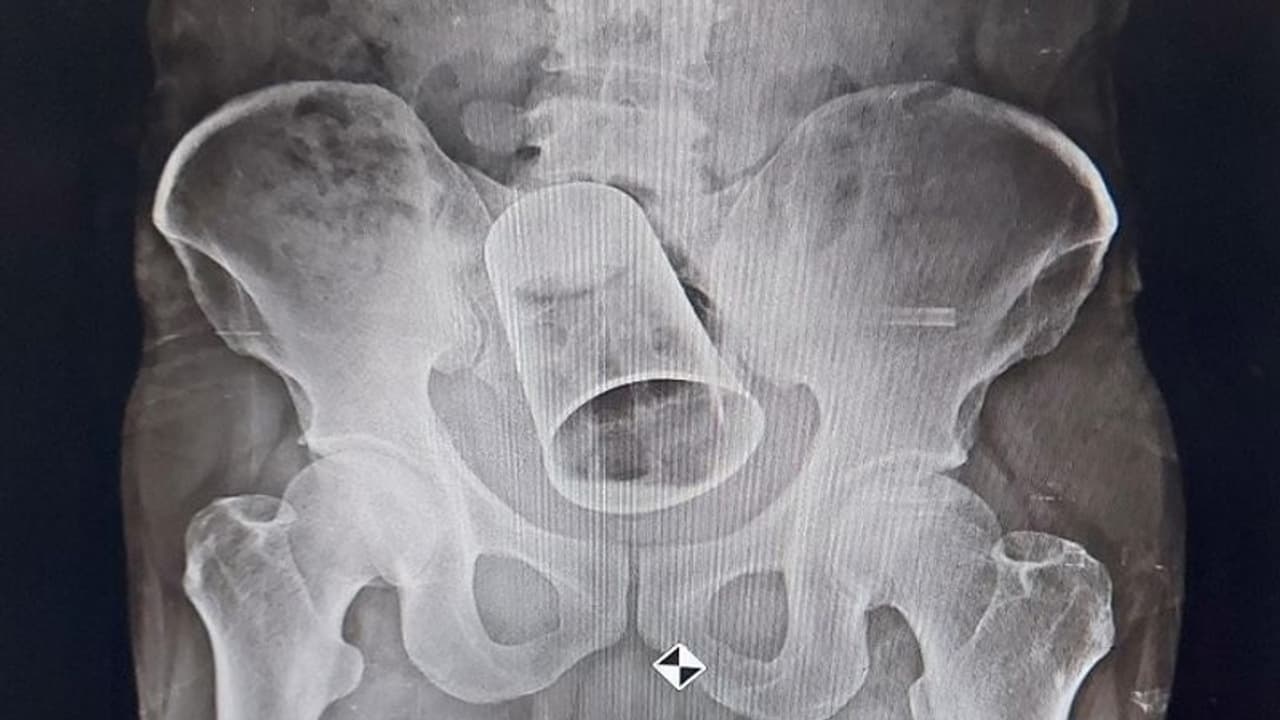

एक्स-रे रिपोर्ट में दिखा ग्लास

चेकअप के बाद डॉक्टरों ने एक्स-रे टेस्ट कराने की सलाह दी। एक्स-रे रिपोर्ट में साफ-साफ दिख रहा था कि उसके आंत में एक ग्लास है। डॉक्टरों ने पहले ग्लास को रेक्टम के रास्ते बाहर निकालने की कोशिश की, लेकिन वे सफल नहीं हुए। इसके बाद मरीज को सर्जरी कराने की सलाह दी गई।